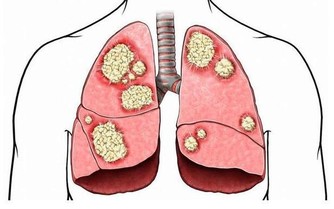

1、抗腫瘤

黃瓜中含有的葫蘆素C具有提高人體免疫功能的作用,達到抗腫瘤目的。此外,該物質還可治療慢性肝炎和遷延性肝炎,對原發性肝癌患者有延長生存期作用。